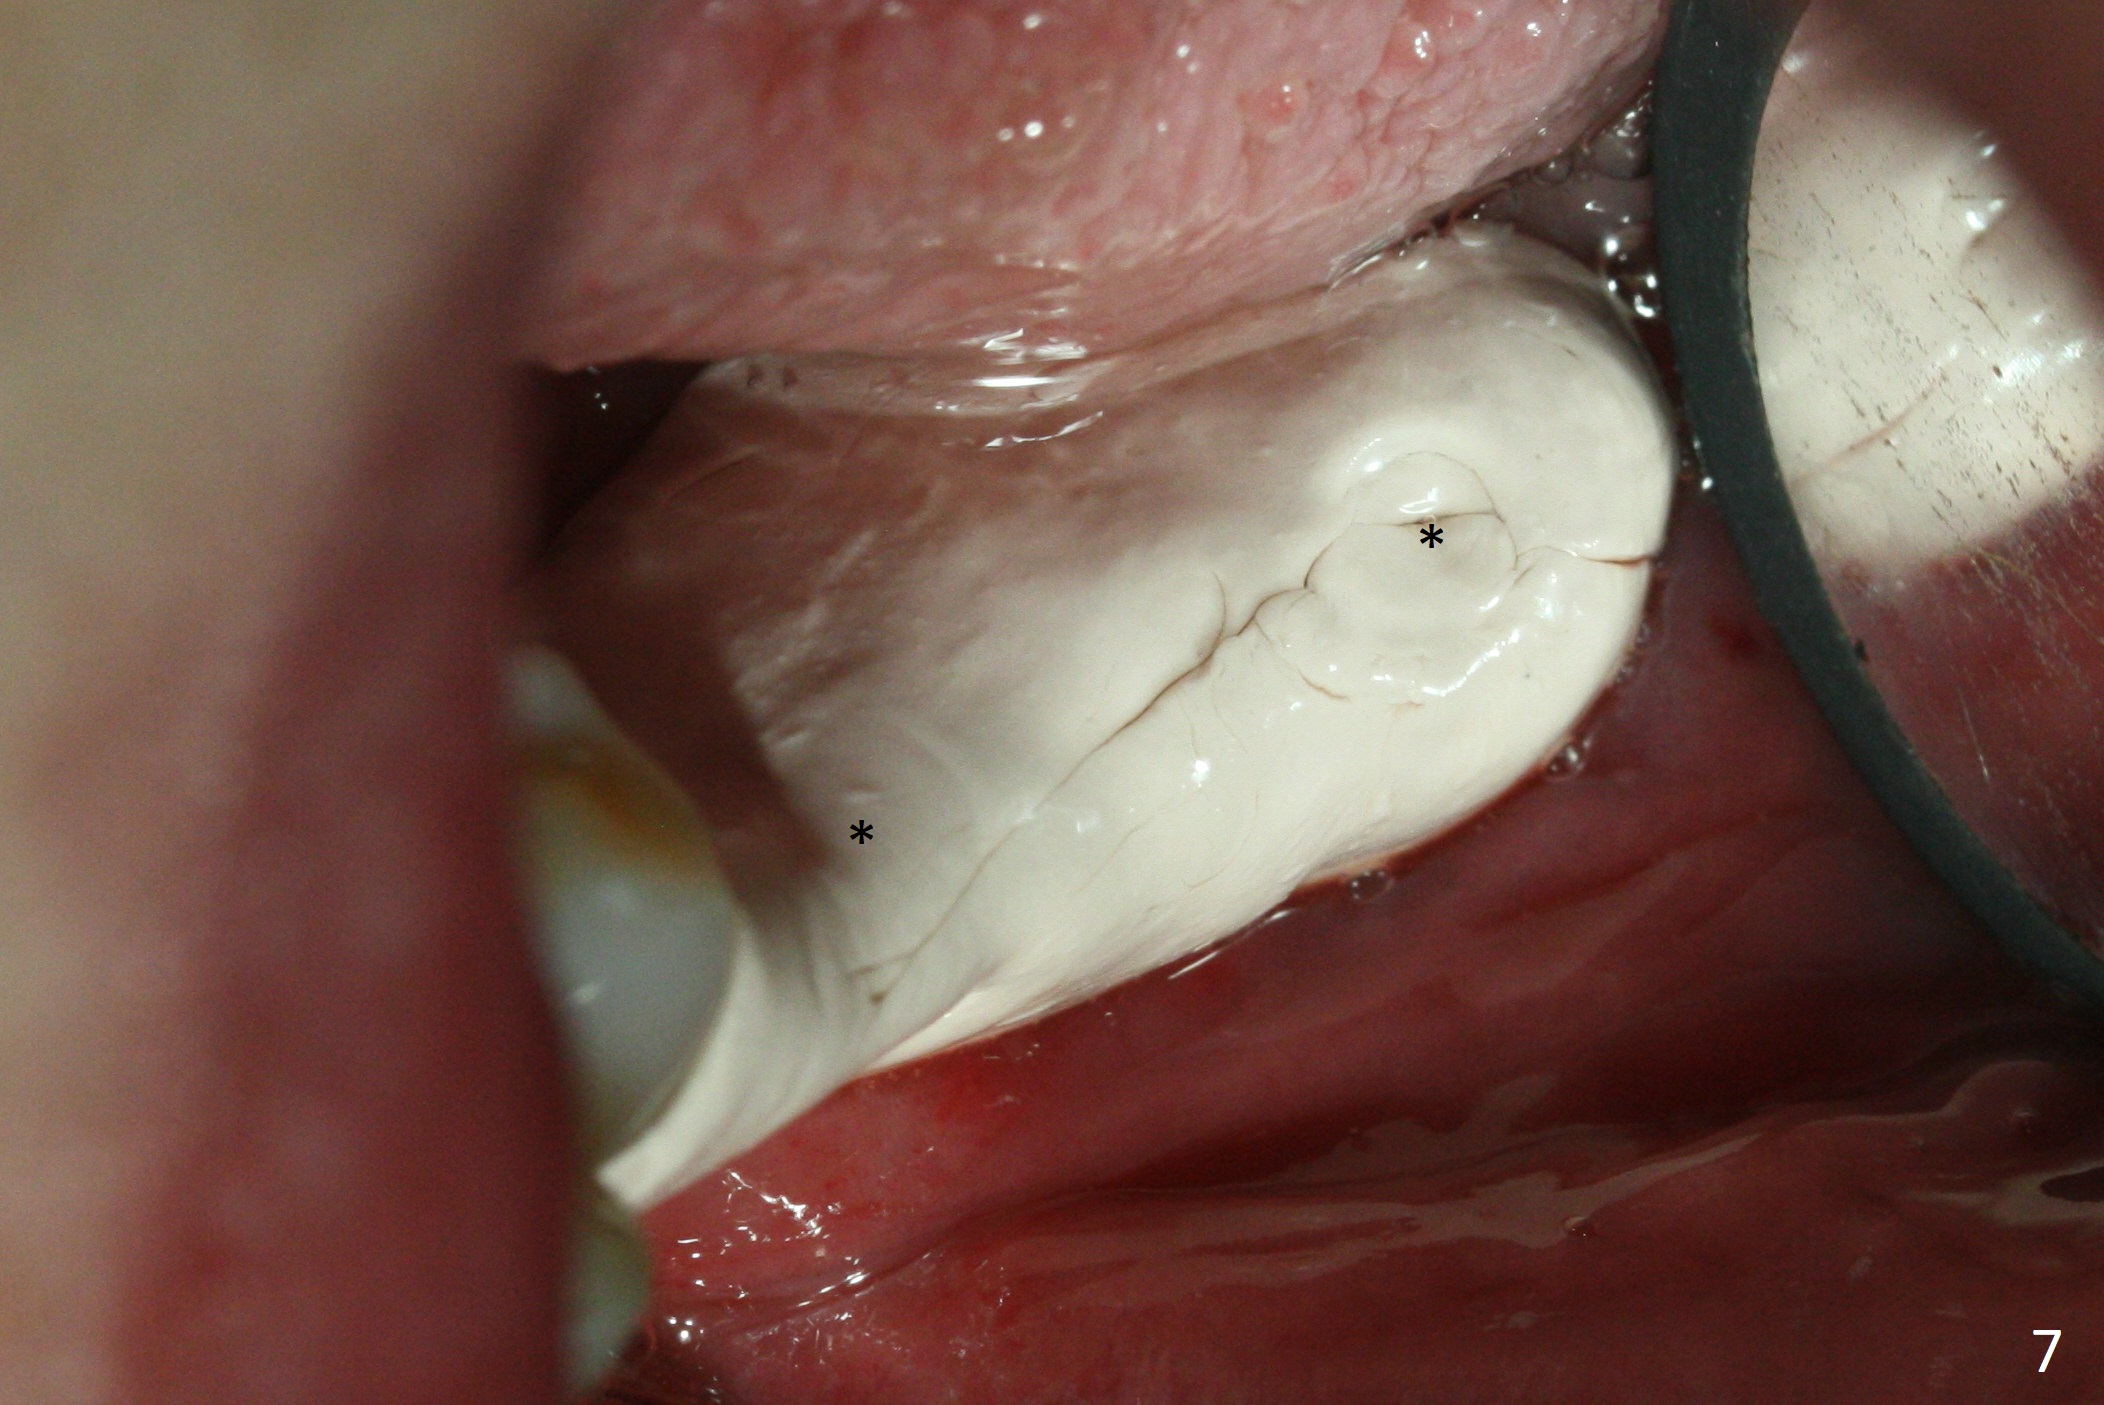

Preop photo shows severe mesial tilt of the tooth #18 (Fig.1). After extraction, the osteotomy is established in the apical end of the socket, where the buccolingual width is limited. It appears that an extra wide implant (5.9 mm) may perforate one of buccolingual plates. On the other hand, the buccal plate (Fig.2 double arrows) is intact and approximately 2 mm tall, whereas the lingual one is thin and lower. Initial osteotomy confirms that bone heights at #18 and 19 are 6 and 8 mm, respectively. Counting 2 mm of the buccal plate and bone graft lingually, a 8 mm long implant may be a practical option at the site of #18. After initial placement of two of 5x8 mm SM implants (Fig.3), the depth of the implant at #19 is adjusted twice (Fig.4,5). With placement of autogenous and allograft (Vanilla, Fig.5 *)) and abutments, a piece of cotton pellet is placed in each abutment well (access, Fig.6 *). Periodontal dressing is applied to the abutment wells for additional retention (Fig.7 *). Due to local poor oral hygiene, splinted provisional is fabricated 4 months postop (Fig.8) in preparation for limited orthodontic uprighting the tooth #20. The patient has pain with mastication at #18 eleven months post cementation (Fig.9). It appears that both of the implants should be removed with immediate replacement and bone graft. Prepare 4 PRF and sticky bone. The new implant will be 5.0 or 5.5x5 mm (Fig.10 green) with 2.3 mm platform (white). A block graft will be harvested from the ipsilateral ramus using 9/8 and 6/5 mm trephine burs for 2-3 mm in depth (Fig.11 blue). The ring graft will be seated around the platform over the implant (Fig.12).